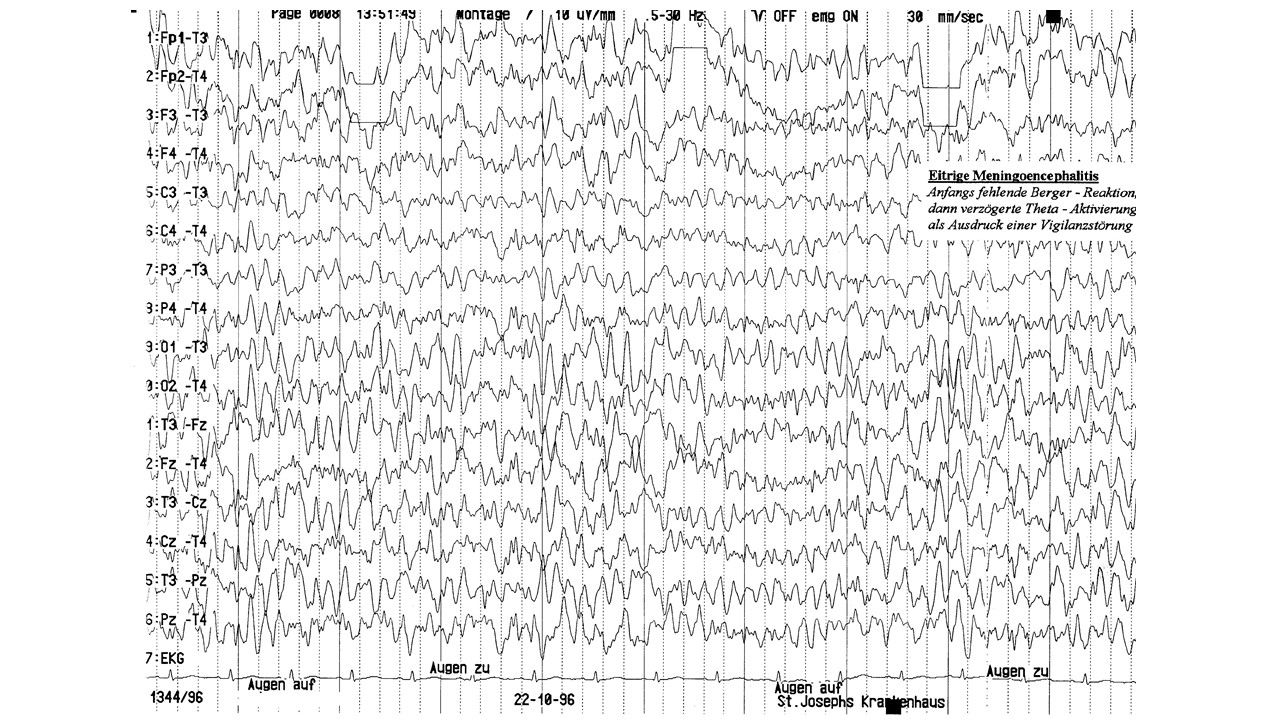

folie158.jpg